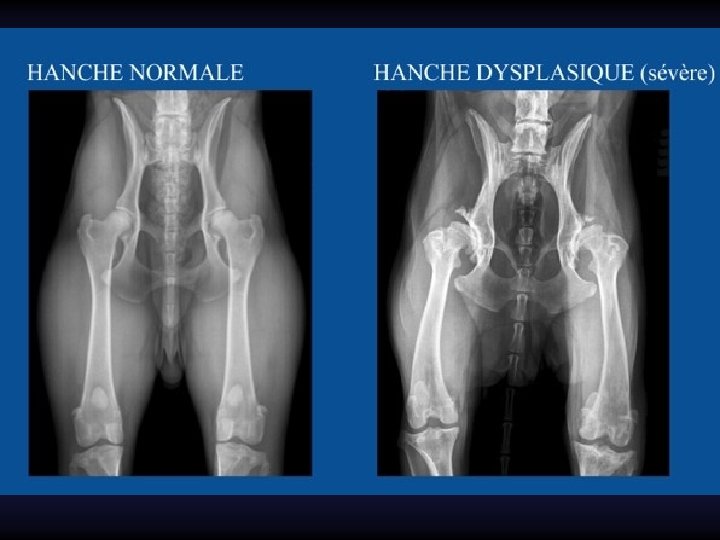

Radiographie